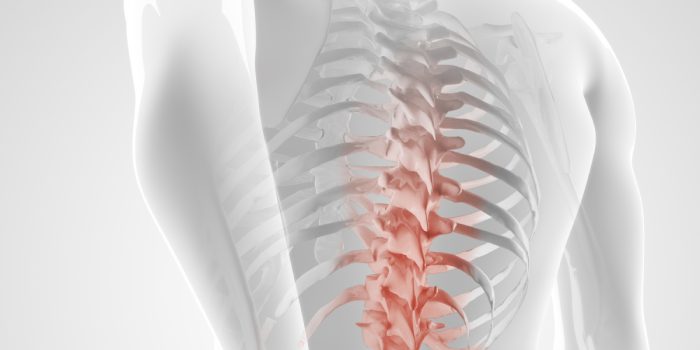

بین مهرههای ستون فقرات که به وسیله مفصلهای کوچکی به هم متصل میشوند، دیسک ها قرار دارند که از وارد آمدن فشار بیش از حد به مهرهها و آسیب جلوگیری میکنند، ولی ضربات و فشارهای بیش از حد به دیسک باعث خروج ماده ژلاتینی میانی آن میشود که میتواند باعث آسیب عصبی و ایجاد درد شود.

همه اجزای ستون فقرات از جمله اعصاب، مفاصل، عضلات، تاندونها و لیگمانها (کشیدگی رباطها) میتوانند باعث درد شوند، درد پشت یا ستون فقرات را به ۴ قسمت گردن درد، درد تنه، درد قسمت تحتانی یا کمر و درد دنبالچه تقسیم می شود.

ممکن است بیماران از یک درد مبهم یا شدید در ناحیه پشت بدن شکایت کنند که این درد میتواند به اندامهای تحتانی یا فوقانی انتشار پیدا کند و از علائم همراه دیگر آن میتوان از بروز ضعف عضلانی و اختلال حس به صورت گزگز و یا بیحسی نام برد.